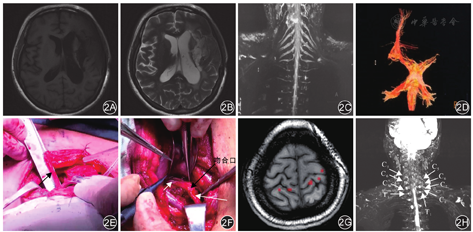

病例1:患者女,50岁,因"脑出血术后14个月伴右侧肢体无力"于2020年8月11日入院。临床表现:右上肢肌痉挛伴右侧肢体偏瘫。入院时查体:神志清楚。左上肢前臂远端残疾,肌力5级、肌张力正常,左下肢肌力、肌张力均正常;右上肢肌力1级、肌张力3级,右下肢肌力4级、肌张力1级。影像学检查:(1)头颅MRI显示左侧基底节区软化灶;(2)头颅MR DTI显示左侧皮质脊髓束较对侧稀疏;(3)臂丛神经MRI显示双侧臂丛上、中、下干对称,左侧C7神经长度5.9 cm,右侧C7神经长度5.8 cm。见图2。

注:C5为颈5神经;C6为颈6神经;C7为颈7神经;C8为颈8神经;T1为胸1神经

2例患者术后健侧上肢均出现疼痛和麻木感,该症状在术后1个月消退;术后患侧上肢肌痉挛症状较术前改善。病例1术后随访12个月,末次随访时左侧(健侧)上肢感觉正常,运动功能正常,肌力5级、肌张力正常;右侧(患侧)上肢感觉正常,近端肌力3级,远端肌力2级,可缓慢完成握拳动作;复查fMRI提示右手活动由两侧初级运动皮层控制。病例2术后随访8个月,末次随访时左侧(健侧)上肢感觉正常,运动功能正常,左侧上肢肌力5级、肌张力正常;右侧(患侧)上肢感觉正常,运动功能在康复中,近端肌力1级,远端肌力0级、肌张力1级。

C7神经移位术后患侧上肢疗效主要分为近期疗效和远期疗效。近期疗效主要表现为上肢痉挛症状的缓解。肌张力通常由位于脊髓中的g神经元回路维持[16],当大脑皮层受到损伤时,g神经元回路不受抑制,肌肉痉挛随之发生。而C7神经含有丰富的g神经元纤维,切断C7神经可阻断g神经元回路,减少牵张反射环路,有助于减轻屈肌痉挛[16]。本研究2例患者术后上肢痉挛症状明显缓解,与既往研究结果相一致。C7神经移位术后远期疗效主要观察肌力的恢复。文献报道C7神经移位术后神经肌肉的恢复分为5期:术后1个月,神经再生轴突生长越过吻合口;术后1~3个月,神经生长至胸大肌、背阔肌;术后3~6个月,神经生长至肱三头肌;术后6~9个月,神经生长至前臂伸腕肌;术后9~12个月,神经生长至前臂伸腕肌、伸指肌[17]。由此可见,术后患侧上肢运动功能的恢复时间常在1年以上。本研究中,病例1患者术后12个月患侧上肢肌力恢复至近端3级和远端2级,可完成缓慢握拳动作,处于神经恢复第5期,术后fMRI结果显示患者右手运动由两侧初级运动皮层支配,提示上肢功能恢复的中枢性代偿;病例2术后8个月随访时,患者近端肌力1级,远端肌力0级,目前处于神经恢复第4期,考虑神经恢复的个体差异,神经恢复相对较慢,但时间未达1年,目前仍在康复中。